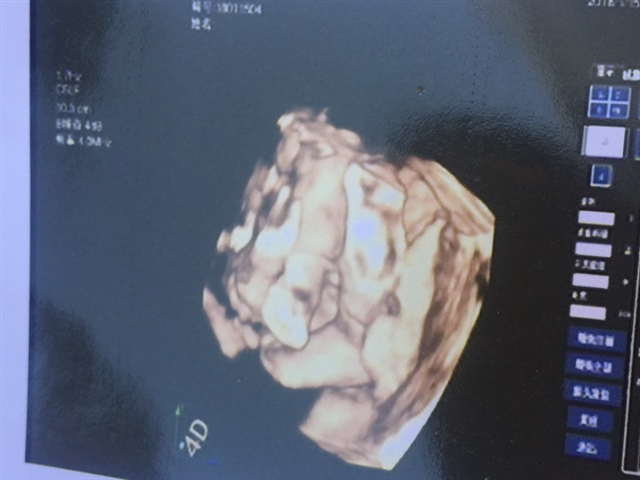

宝宝2个月16天

💓天使的翅膀💗[帖主]:有找熟人问了说是跟儿子一样,我在纠结最后一张照片照什么,看过去怎么像女孩的生殖器官,哈

最后一张应该是两条腿跟小脚丫吧,夹这么紧看不出男女

💓天使的翅膀💗[帖主]:那个裂痕会不会显示的是生殖器官?

女孩吧